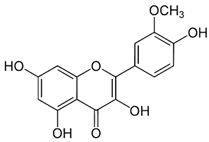

| Sr. No. | Name | PubChem ID | MF | MW | Canonical SMILES | Structure |

|---|---|---|---|---|---|---|

| 1 | Apigenin | 5280443 | C15H10O5 | 270.24 | C1=CC(=CC=C1C2=CC(=O)C3=C(C=C(C=C3O2)O)O)O |  |

| 2 | Caffeic acid | 689043 | C9H8O4 | 180.16 | C1=CC(=C(C=C1C=CC(=O)O)O)O |  |

| 3 | Catechin | 9064 | C15H14O6 | 290.27 | C1C(C(OC2=CC(=CC(=C21)O)O)C3=CC(=C(C=C3)O)O)O |  |

| 4 | Chlorogenic acid | 1794427 | C16H18O9 | 354.31 | C1C(C(C(CC1(C(=O)O)O)OC(=O)C=CC2=CC(=C(C=C2)O)O)O)O |  |

| 5 | Digalacturonic acid | 439694 | C12H18O13 | 370.26 | C1(C(C(OC(C1O)OC2C(C(C(OC2C(=O)O)O)O)O)C(=O)O)O)O |  |

| 6 | Ferullic acid | 445858 | C10H10O4 | 194.18 | COC1=C(C=CC(=C1)C=CC(=O)O)O |  |

| 7 | Gallic acid | 370 | C7H6O5 | 170.12 | C1=C(C=C(C(=C1O)O)O)C(=O)O |  |

| 8 | Iso-quercetin | 10813969 | C21H20O12 | 464.4 | C1=CC(=C(C=C1C2=C(C(=O)C3=C(C=C(C=C3O2)O)O)OC4C(C(C(C(O4)CO)O)O)O)O)O |  |

| 9 | Luteolin | 5280445 | C15H10O6 | 286.24 | C1=CC(=C(C=C1C2=CC(=O)C3=C(C=C(C=C3O2)O)O)O)O |  |

| 10 | Myricetin | 5281672 | C15H10O8 | 318.23 | C1=C(C=C(C(=C1O)O)O)C2=C(C(=O)C3=C(C=C(C=C3O2)O)O)O |  |

| 11 | p-coumaric acid | 637542 | C9H8O3 | 164.16 | C1=CC(=CC=C1C=CC(=O)O)O |  |

| 12 | Protocatechuic acid | 72 | C7H6O4 | 154.12 | C1=CC(=C(C=C1C(=O)O)O)O |  |

| 13 | Quercetin | 5280343 | C15H10O7 | 302.23 | C1=CC(=C(C=C1C2=C(C(=O)C3=C(C=C(C=C3O2)O)O)O)O)O |  |

| 14 | Resorcinol | 5054 | C6H6O2 | 110.11 | C1=CC(=CC(=C1)O)O |  |

| 15 | Rutin | 5280805 | C27H30O16 | 610.5 | CC1C(C(C(C(O1)OCC2C(C(C(C(O2)OC3=C(OC4=CC(=CC(=C4C3=O)O)O)C5=CC(=C(C=C5)O)O)O)O)O)O)O)O |  |

| 16 | β-Carotene | 5280489 | C40H56 | 536.9 | CC1=C(C(CCC1)(C)C)C=CC(=CC=CC(=CC=CC=C(C)C=CC=C(C)C=CC2=C(CCCC2(C)C)C)C)C |  |

| 17 |  | 222284 | C29H50O | 414.7 | CCC(CCC(C)C1CCC2C1(CCC3C2CC=C4C3(CCC(C4)O)C)C)C(C)C |  |